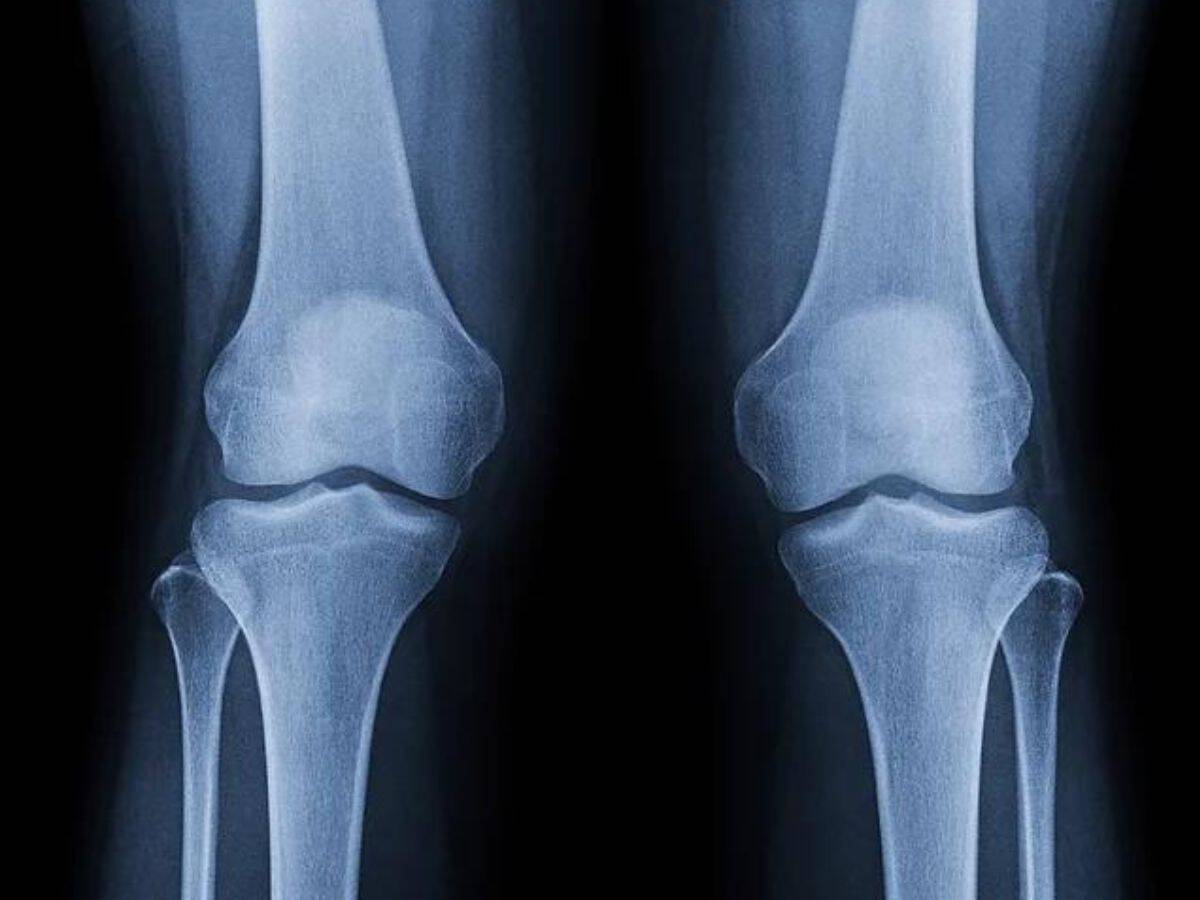

Osteoarthritis (OA) stands as a prevalent cause of knee pain among individuals over 50. It entails the deterioration of the protective joint cartilage, essential for smooth joint movement and weight-bearing. OA often manifests earlier in those who are obese, chronic smokers, or lead sedentary lives.

While total knee arthroplasty undoubtedly offers remarkable relief to patients with severe OA, studies indicate a dissatisfaction rate as high as 30-20%. Many patients who undergo this procedure struggle with adhering to the rigorous postoperative rehabilitation spanning several months, which compounds their distress.